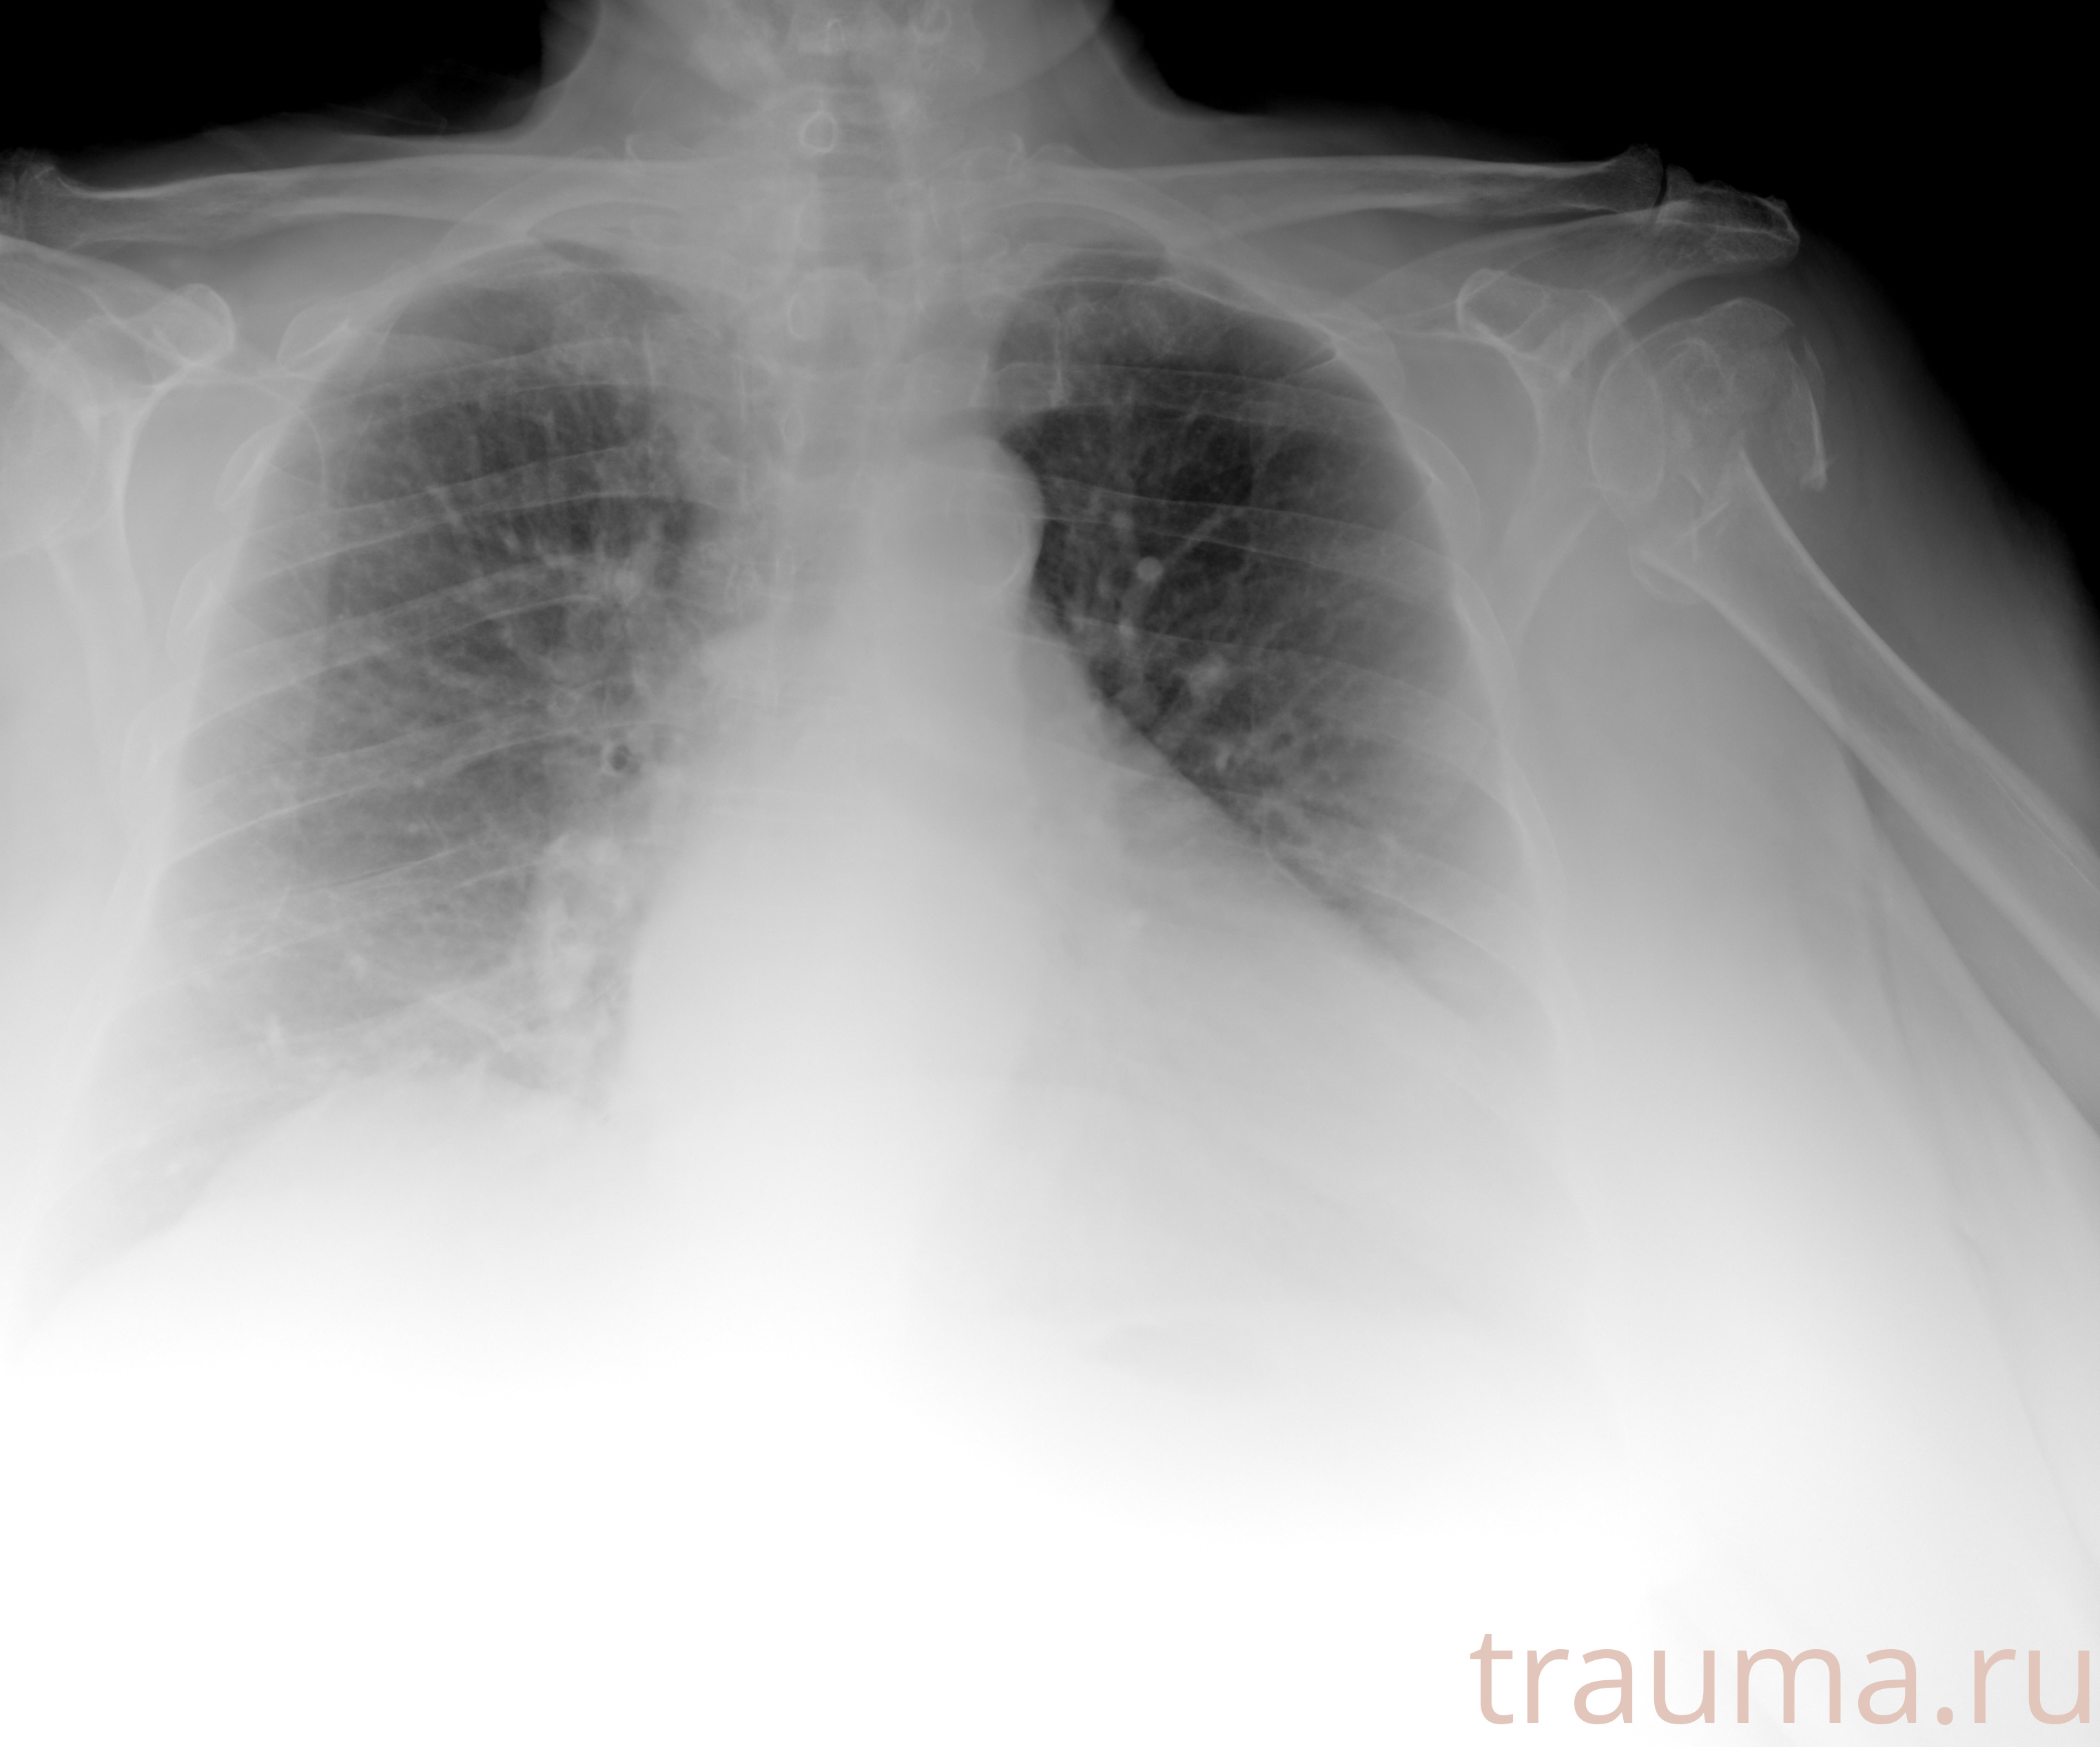

Рентген на дому: по вашему адресу приезжает врач-рентгенолог, травматолог-ортопед с мобильным рентгеновским аппаратом, проводит диагностику травмы или заболевания, делает необходимые рентгенограммы, дает рекомендации по дальнейшему лечению. Получить качественные снимки в домашних условиях возможно благодаря уникальной методике, разработанной МосРентген Центром для института  Склифосовского

при переломе шейки бедра и пневмонии от компании МосРентген Центр - партнера Института имени Склифосовского